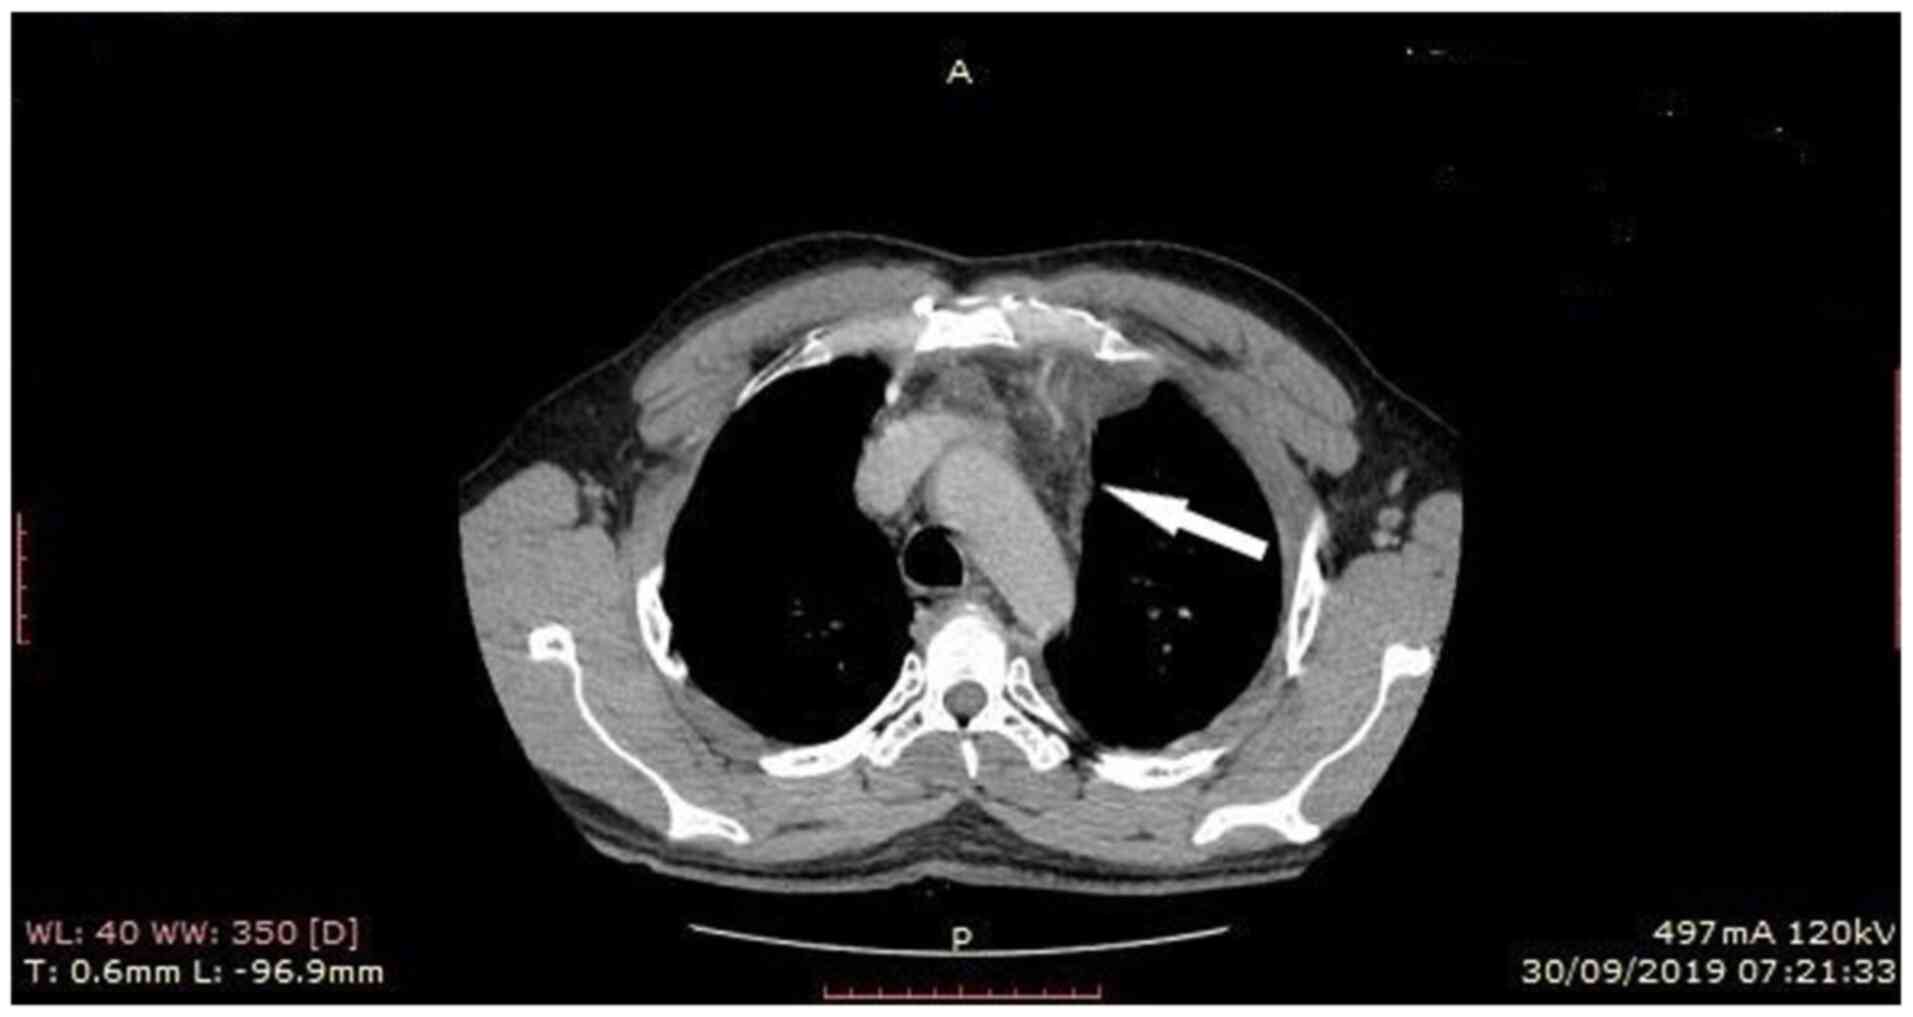

The patient underwent computed tomography (CT) of the chest showing consolidation in the left lower lobe with left pleural effusion, edema of the soft tissue adjacent to the first sternocostal joint and heterogeneity, and invasion of the retrosternal fat (Figs. 2 and 3). In addition, the patient underwent magnetic resonance imaging (MRI) of the chest, to obtain detailed information regarding the pleura and mediastinum, that revealed abnormal soft tissue with dimensions at transverse level 7.0x1.3 cm, containing cystic lesions, adjacent to the first sternocostal joint, indicating inflammation in sternocostal cartilage. MRI also revealed contrast enhancement of the ipsilateral mediastinal pleura, imaging compatible with mediastinitis (Fig. 4).

Figure 2

Chest computed tomography (mediastinal window) shows edema of the soft tissue adjacent to the first sternocostal joint and retrosternal fat heterogeneity/invasion. A, anterior; P, posterior.